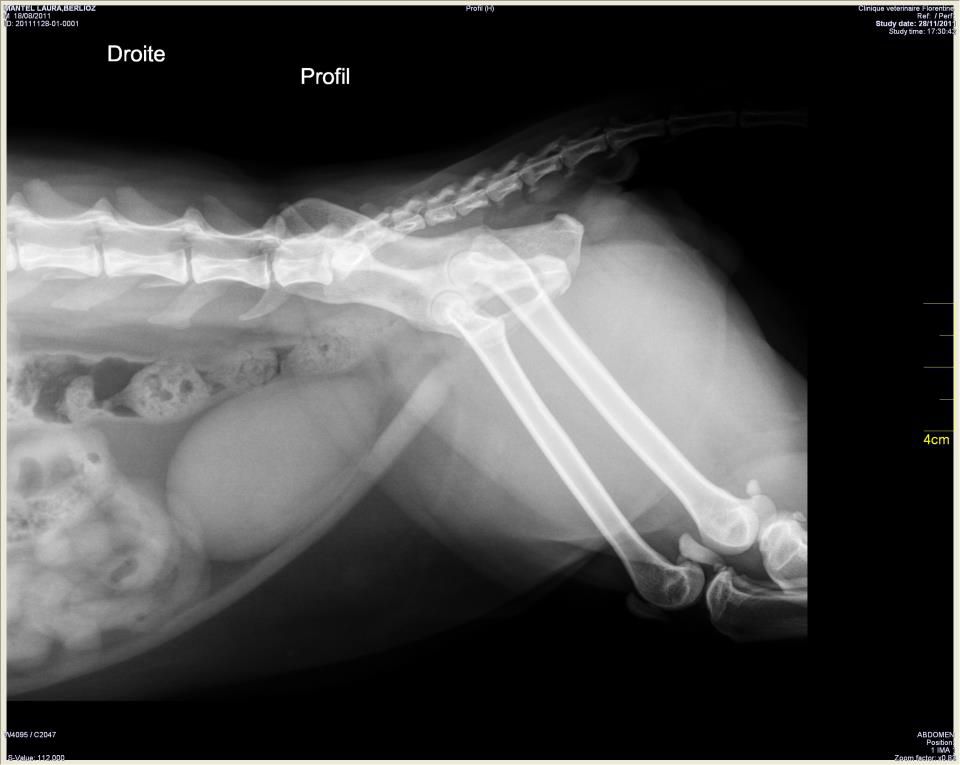

| Dire merci | oui je penserai aussi a calculs.... une echo te renseignera vite fait. si ce sont des calculs: rincage de la vessie sous anesthesie , puis croquettes urinary |

| Dire merci | Grand classique avec les chats! Le chat bouché! Des calculs qui se trouvent dans la vessie et passent parfois dans la "tuyauterie" pour sortir dehors avec l'urine. Sauf que parfois, ces calculs sont trop gros et bouchent le tuyau, justement. D'où le terme de "chat bouché". Dans la plupart des cas, ce sont des calculs acides. Le traitement de fond (une fois que le chat a été débouché (hospitalisation, sonde, perfusion, etc, etc... ) consiste à lui donner une alimentation qui modifie le PH de l'urine dans la vessie. Pour cela, tu achètes soit des croquettes à 10€/kg au moins chez le veto Soit, comme moi j'avais fait et ça marche très bien aussi, tu choisis en supermarché les aliments avec la mention "pour un système urinaire sain" qui sont dans les 3-4€/kg (déjà pas donné, mais c'est le haut de gamme). Vu que ton chat n'est pas encore "physiquement bouché" mais qu'il semble déjà qu'il pisse des calculs, tu devrais le mettre dès que possible à ce genre d'alimentation. NB : inutile de mettre sous ce genre d'alimentation des chats sans soucis : s'ils n'ont pas de calculs acides, rendre l'urine plus basique risque de faire apparaitre d'autre calculs, basiques ceux-là, et que pour le coup, on ne sait pas dissoudre... |

| Dire merci | Des nouvelles? parce que les calculs ne sont pas forcément dans la vessie, mais peuvent se foutre dans l'urètre... C'est là que ça devient moins drôle... Dans la vessie on voit rien du tout, sauf qu'un calcul énorme a finit par sortir après 2 lavages et un coup d'ultrasons ![]() ![]() |